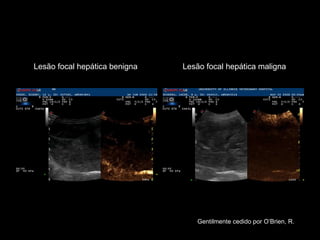

Aplicações clínicas Medicina humana x Veterinária: detecção e caracterização de mudanças na perfusão de vários órgãos incluindo o coração Maioria dos trabalhos focados no estudo do fígado (a dupla vascularização hepática aumenta acurácia na diferenciação de lesões benignas e malignas elevando-a a níveis histológicos!)

Lesão focal hepática benigna Lesão focal hepática maligna Gentilmente cedido por O’Brien, R.

Na medicina veterinária:  Caracterização lesões fígado, baço, próstata, linfonodos, detecção infarto e lesões focais no rim em cães Quantificação de perfusão de um tecido ou órgão através da avaliação quantitativa de curvas de tempo-intensidade (TIC) em uma região de interesse (ROI) O’Brien et al., 2004; Salwei et al., 2005; Kutara et al., 2006; Quaia et al., 2006; Ohlerth et al., 2008; Rossi et al., 2010; Nakamura et al., 2010; Vignoli et al., 2010.